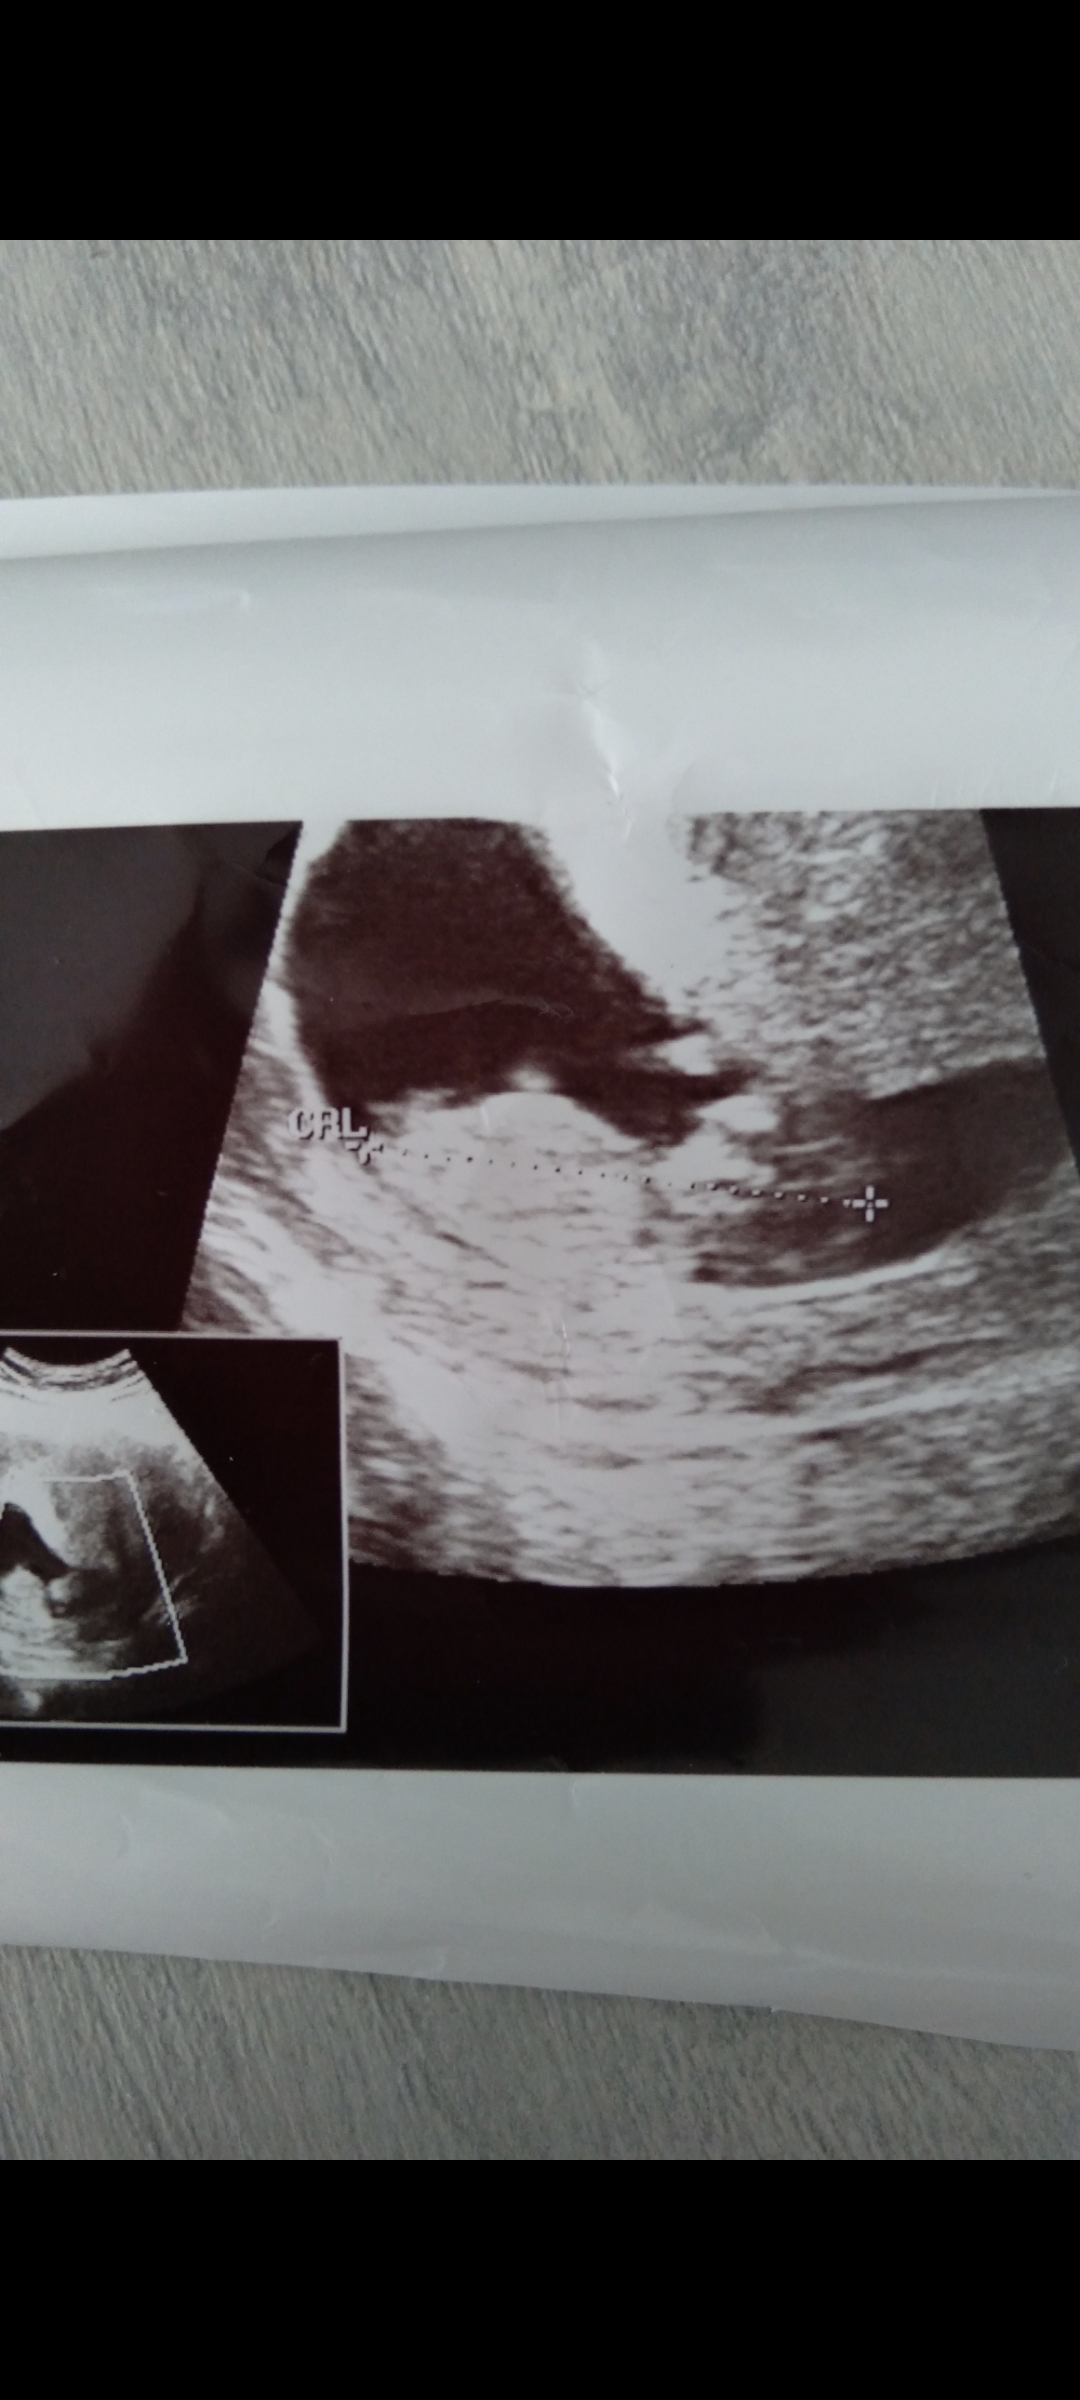

• Screenshot_20221119-153255_Gallery.jpg

Screenshot_20221119-153255_Gallery.jpg

382 KB · Görüntüleme: 151